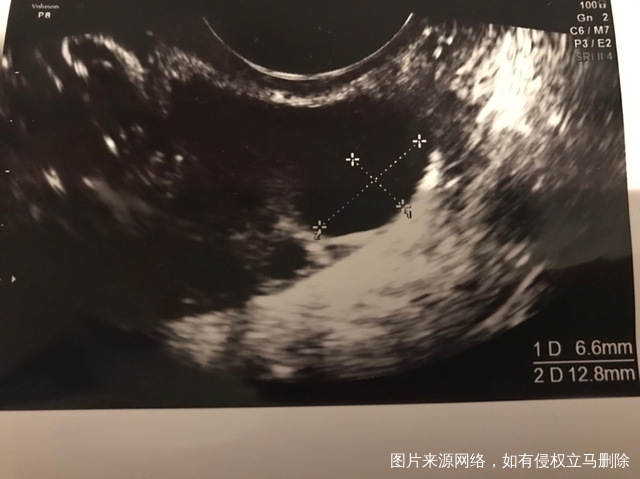

月经第三天发现有两个大卵泡见图一个12866